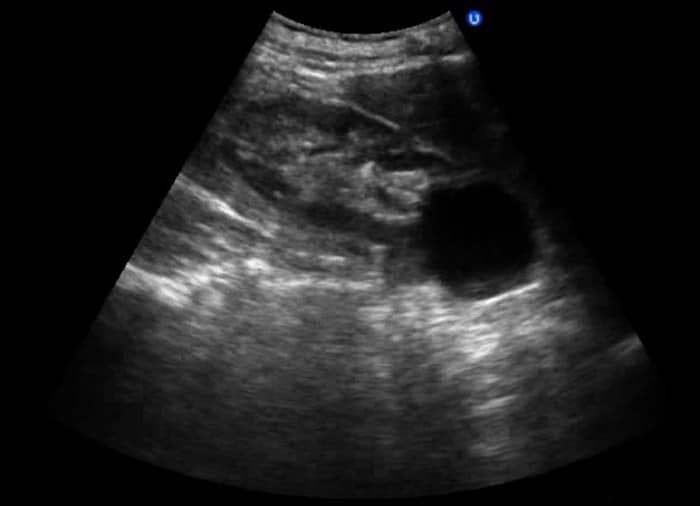

При ультразвуковом обследовании кисты выглядят как анэхогенные образования без кровеносных сосудов.

В нормальном состоянии почки здорового человека симметрично расположены, имеют четкую структуру и овальную форму. При их сканировании не отражаются ультразвуковые волны. Но при патологических изменениях или заболеваниях почек УЗИ может обнаружить гипер- или гипоэхогенные тела.

Гипоэхогенные образования (включения, тела) – это участок органа или полости имеющий сниженную акустическую плотность, по сравнению с окружающей его тканью. На мониторе они выглядят как черные пятна с четкими или размытыми краями имеющие акустическую тень или без таковой.